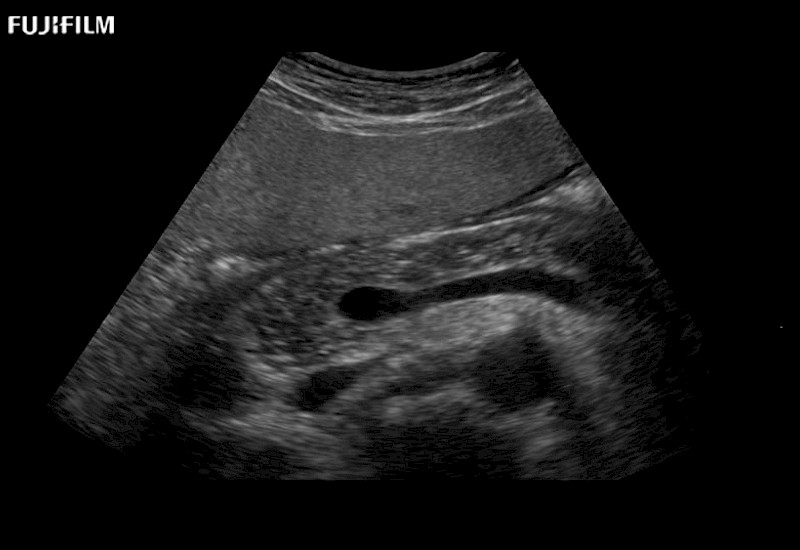

for use during open and laparoscopic procedures: Tumor localization & staging, Ablation, Resection, Biopsy, Transplant, Abdominal exploration, Robotic surgery

Our dedication to Surgical Oncology allows us to offer superior image quality, outstanding system reliability and intuitive use of cutting edge technology.